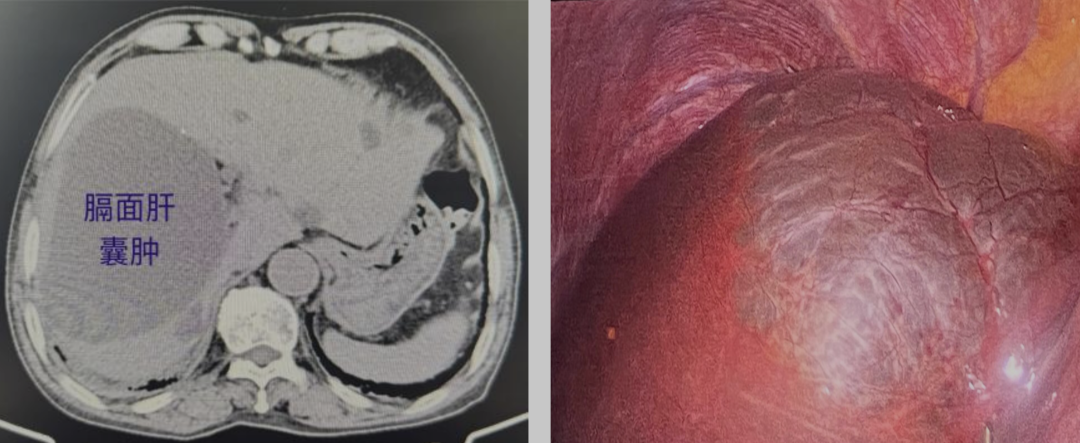

他的膈面肝囊肿

两年内做了两次开窗引流

长在膈面的肝囊肿因位置特殊,是肝囊肿治疗中的“硬骨头”,传统B超穿刺硬化、腹腔镜开窗引流等方式,都难逃高复发困境。因膈面肝囊肿紧邻膈肌,常规开窗术后,膈肌会像塌下来的天花板一样贴合肝脏表面,刚打开的囊腔极易再次封闭,这也是其复发率远高于普通肝囊肿的关键,不少患者因此反复手术。

硬化剂囊肿硬化:先以硬化剂让囊肿壁失去分泌功能,从源头减少囊液;

腹腔镜开窗引流:再通过腹腔镜微创充分开窗,彻底排出囊液;